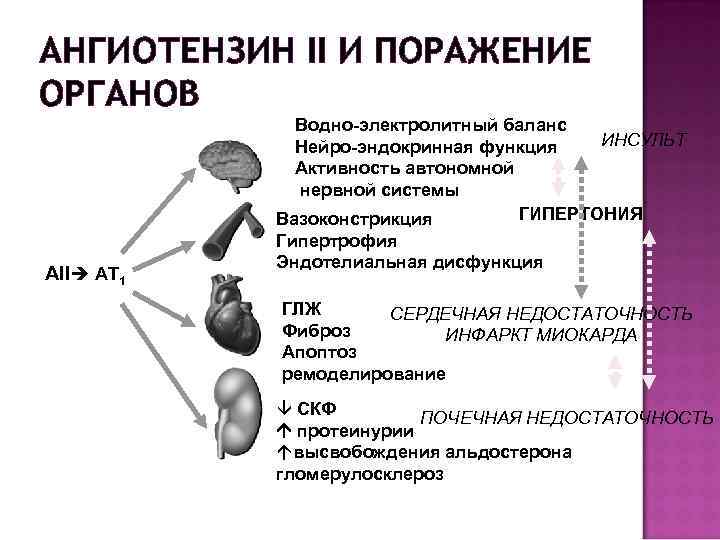

АНГИОТЕНЗИН II И ПОРАЖЕНИЕ ОРГАНОВ АII AT 1 Водно-электролитный баланс ИНСУЛЬТ Нейро-эндокринная функция Активность автономной нервной системы ГИПЕРТОНИЯ Вазоконстрикция Гипертрофия Эндотелиальная дисфункция ГЛЖ СЕРДЕЧНАЯ НЕДОСТАТОЧНОСТЬ Фиброз ИНФАРКТ МИОКАРДА Апоптоз ремоделирование СКФ ПОЧЕЧНАЯ НЕДОСТАТОЧНОСТЬ протеинурии áвысвобождения альдостерона гломерулосклероз

АНГИОТЕНЗИН II И ПОРАЖЕНИЕ ОРГАНОВ АII AT 1 Водно-электролитный баланс ИНСУЛЬТ Нейро-эндокринная функция Активность автономной нервной системы ГИПЕРТОНИЯ Вазоконстрикция Гипертрофия Эндотелиальная дисфункция ГЛЖ СЕРДЕЧНАЯ НЕДОСТАТОЧНОСТЬ Фиброз ИНФАРКТ МИОКАРДА Апоптоз ремоделирование СКФ ПОЧЕЧНАЯ НЕДОСТАТОЧНОСТЬ протеинурии áвысвобождения альдостерона гломерулосклероз